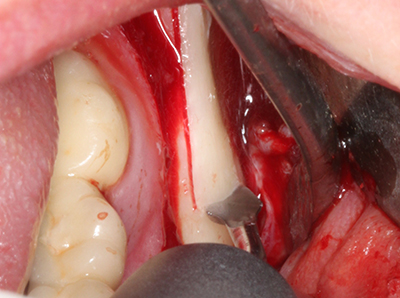

Indication: Apical resection

When surgical procedures are performed on bone in the immediate vicinity of sensitive structures such as blood vessels or nerves, rotary instruments pose a significant risk of iatrogenic injury. Piezoelectric devices can be helpful for preparation of bone covers and removal of hard tissue close to nerves, particularly for exposure of nerves after iatrogenic injury but also during nerve lateralization for resective and reconstructive procedures or implant placement (Fig. 17-20). Light contact between the piezotip and the nerve does not generally result in damage but proceeding incautiously with saw-like motions or attachments where a residual bone substrate remains may cause temporary or even permanent nerve damage. However, the risk of damage is considered to be substantially lower than when using saws or milling instruments (Pereira, Gealh et al. 2014).